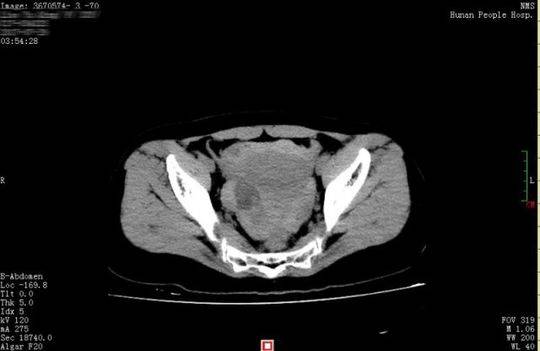

【直报网北京8月23日讯】(潇湘晨报)黄体囊肿破裂是妇科常见的急腹症之一,常见于20~40 岁的育龄期女性。此病最常见的诱因是性生活时女性生殖器官充血,加上男方动作粗鲁,导致女方腹部受到强烈的冲击,表现为不同程度的腹痛和腹腔内出血,严重的可出现失血性休克,因此被称为女性" 青春杀手"。七夕佳节即将来临,湖南省人民医院妇科专家提醒,情人节约会别太" 生猛",小心黄体囊肿破裂。 26 岁的小晴和28 岁的小东是一对新婚夫妇,因工作的缘故两地分居。8 月16 日,近半年未见丈夫的小晴回到长沙。晚上,小别胜新婚的两人免不了亲热一番。谁知激情过后,小晴出现下腹部疼痛,而且越痛越厉害,只得来到湖南省人民医院天兴阁院区急诊科就诊。尿妊娩检查结果为阴性,而腹部CT 提示盆腔、腹腔有大量积血、积液,随即转入妇科。黄薇副主任医师接诊后发现,小晴面色苍白,浑身大汗淋漓,脉搏为102 次/ 分,呼吸22 次/ 分,血压89/54mmgH, 血红蛋白为79g/l, 已达到失血性休克的标准。 黄薇立即为小晴进行诊断性腹腔镜手术,术中发现腹腔内积血约1500ml,接近她全身总血量的40%," 再晚一点来,就会危及生命了"。医生还发现,在她右侧卵巢有一个直径3cm 左右的黄体囊肿表面有破口,破口有血块附着,还有活动性出血。黄薇立即为她施行黄体囊肿剥除和创面缝合止血手术,恢复了卵巢的正常形态。 黄薇介绍,女性月经来之前的7~10 天左右,卵巢会有一个生理性的黄体囊肿形成。黄体破裂最易发生在月经中期后7~10 天,此期也称黄体期。通常黄体囊肿破裂有两种情况:一是黄体发育时破坏了卵巢的小血管,黄体内部出血,导致内部压力上升,从而发生自发性破裂,此种情况非常少见。第二种是因外力作用,最常见的诱因是性生活时女性生殖器官扩张充血,黄体内张力升高,加上男方动作粗鲁,女方腹部受到强烈的冲击而导致黄体破裂, 此种占黄体囊肿破裂的大多数;另外,在黄体期剧烈跳跃、奔跑、用力咳嗽或解大便时腹腔内压力升高也可能导致黄体破裂。 黄薇特别提醒:七夕佳节将至,恋人们在黄体期同房一定要悠着点,尤其是男方要动作轻柔,尽量少更换姿势,以免发生黄体囊肿破裂出血。